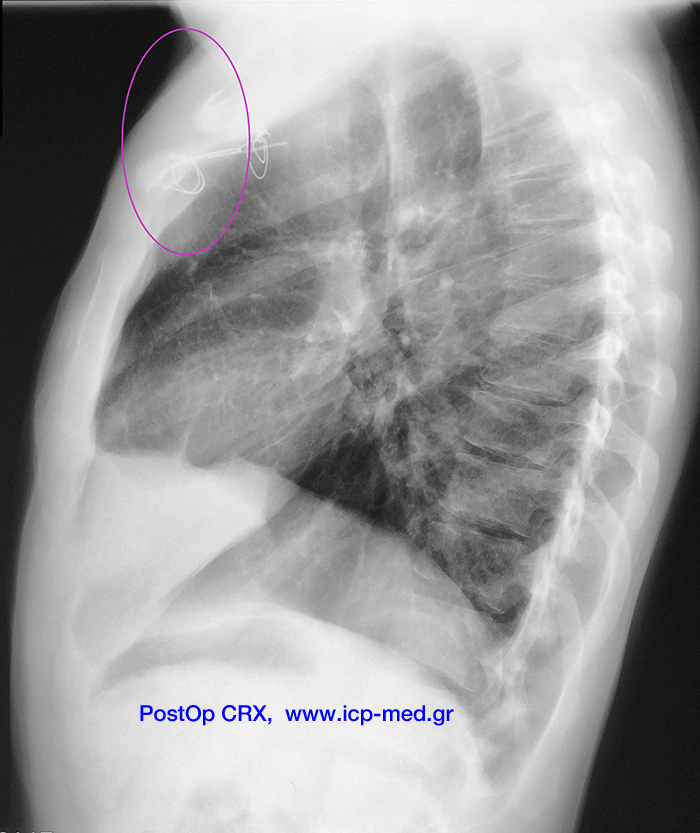

Χονδροσάρκωμα προσθίου Θωρακικού Τοιχώματος

13. Μτχ/κή ακτ/φία (πλαγία): Επισημαίνεται η περιοχή της εκτομής